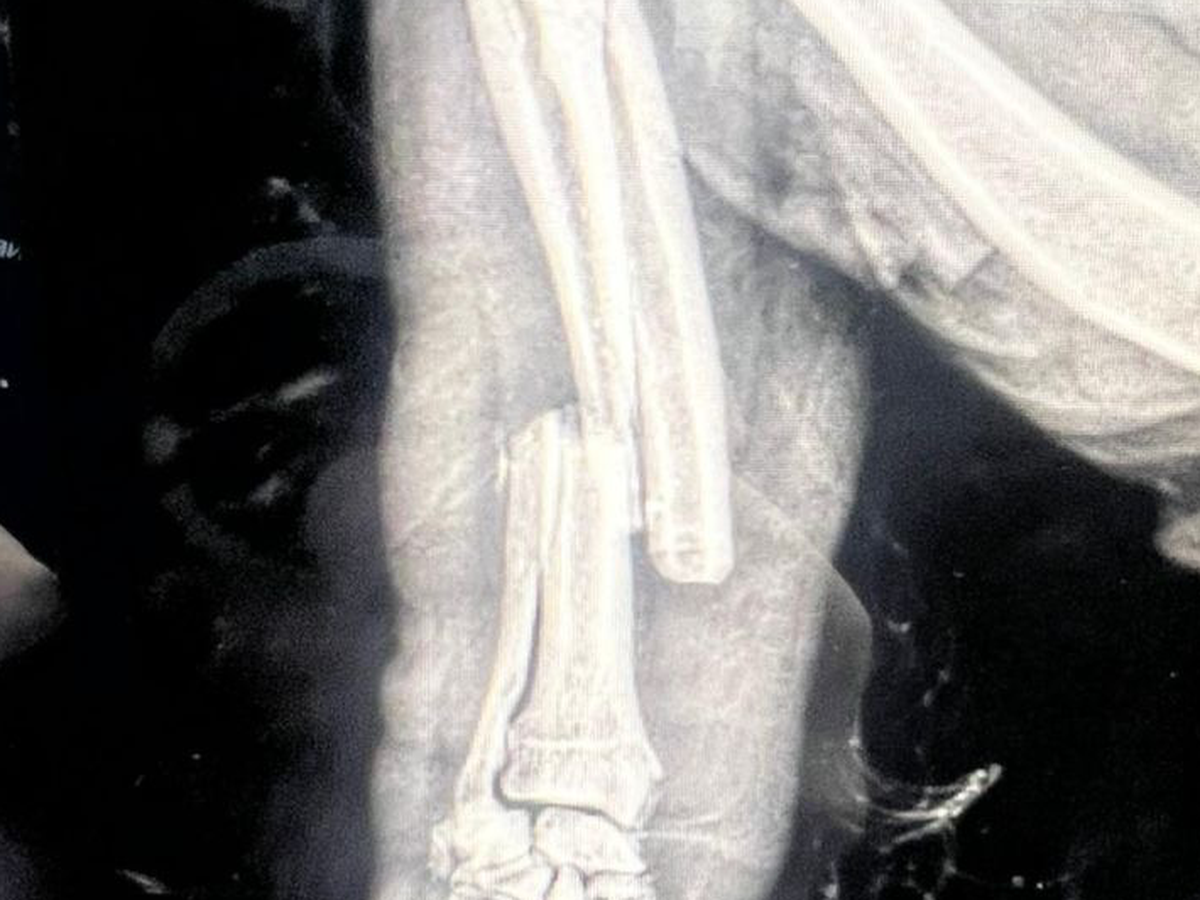

Hi my name is Coral and I’m an eighty year old living with my lovely Cavapoo called Rara. On Friday afternoon she was attacked by two Stafford/Bullie type on a bus in Brighton. She is being cared for at a very caring vets in Brighton but the bill is escalating due to the fact that she is on intravenous medication for pain relief, antibiotics and fluids waiting for an operation to pin and plate her lower front leg that has breaks in her Tibia and Fibula. The operation is scheduled on Wednesday and if there is no infection in the bone from the bit they are hoping to save her leg from amputation. I had pet insurance but the maximum for treatment is £1000 and this will run into many thousands. Any help would be so appreciated.